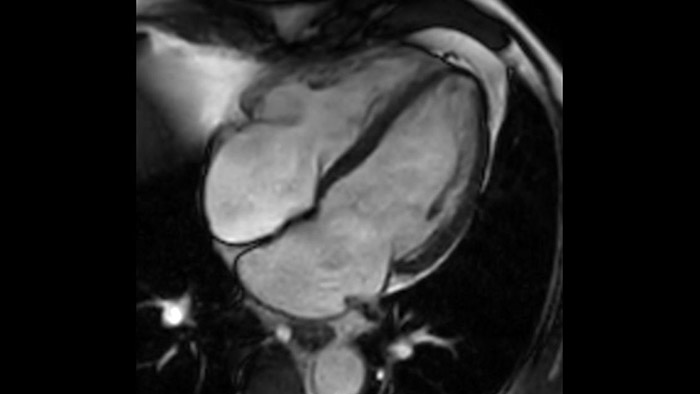

La diagnostica odierna spesso non è in grado di rilevare le disfunzioni cardiache fino a quando non si manifestano sintomi. MyoStrain valuta la deformazione del miocardio in 48 segmenti cardiaci e fornisce ai medici uno strumento diagnostico utile per identificare con anticipo la disfunzione funzionale prima che il cuore nel suo complesso sia compromesso.

La diagnostica tradizionale non offre la visibilità necessaria per vedere gli effetti di un trattamento cardiaco o individuare disfunzioni prima che si verifichino i sintomi. Combinando la sequenza di acquisizione MRI Fast-SENC di Philips con lo strumento di analisi MyoStrain di Myocardial Solutions, i lievi cambiamenti precoci nella funzione cardiaca possono essere misurati direttamente.

L'utilità diagnostica e prognostica della RM cardiaca è in continua crescita. È possibile valutare l'anatomia e la funzionalità cardiache utilizzando acquisizioni cine, ottenere informazioni sulla perfusione e vitalità del tessuto cardiaco, visualizzare potenziali edema con la sequenza Black Blood, accedere e persino quantificare la caratterizzazione dei tessuti con CardiacQuant.

IntelliSpace Portal MR CaaS5,6 Strain7 supporta nella diagnosi e nel monitoraggio dei pazienti fornendo parametri globali di strain, quali strain longitudinale globale (GLS), strain circonferenziale globale (GCS) e strain radiale globale (GRS), utilizzando immagini RM in asse corto e lungo e descrivendo inoltre la deformazione del miocardio, come il suo accorciamento, ispessimento e allungamento durante il ciclo cardiaco.